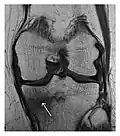

a

b

Figure 14: Subcapital insufficiency fracture in a 55-year-old man with a left hip pain without a history of trauma. Anteroposterior and Lauenstein view radiographs centered on the left hip do not show an obvious fracture line, but mild acetabular osteophytosis was noted consistent with hip osteoarthritis (not shown). (a) Coronal T1-weighted MRI shows a linear low-signal band through the femoral neck corresponding to a fracture line (arrowheads). (b) Bone scintigraphy shows focal uptake (arrow) corresponding to the fracture.[1]